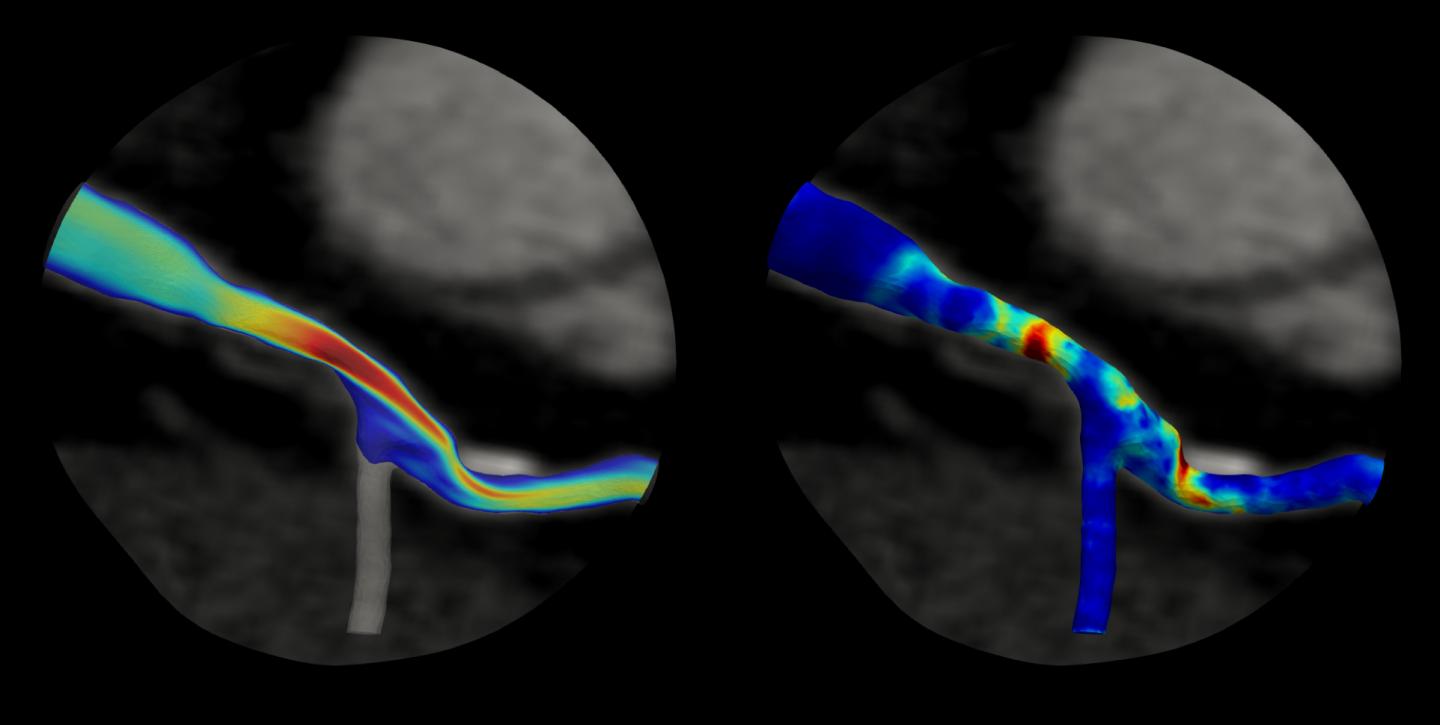

"Recent breakthroughs have presented the opportunity to segment vulnerable plaques from CT scans and identify material constituents, including lipid and calcium content, and fibrous caps, from which patient-specific, computational models can be formulated and the biomechanical stress in the plaque calculated," Hughes said.

The new insights gained from this project will integrate lesion geometry, plaque characteristics and hemodynamic (blood flow) forces into a biomechanical stress analysis aided by deep-learning artificial intelligence methods and could lead to improved noninvasive simulation-based tests to better identify coronary artery plaques at risk of rupture in individual patients.